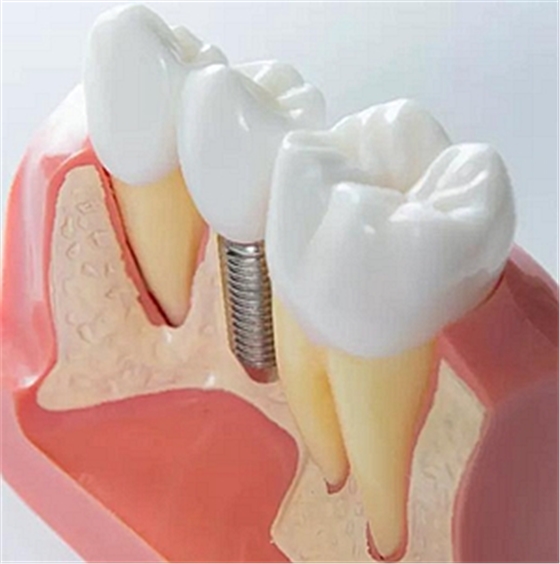

上頜后牙缺失患者常由于先天性上頜竇底位置過(guò)低、牙槽骨嚴(yán)重吸收、萎縮等原因, 使骨量高度不足。直接植入種植體易穿入上頜竇引起感染等并發(fā)癥, 導(dǎo)致種植失敗。上頜竇底提升技術(shù)(Maxillary Sinus FloorLifting)是采用外科手術(shù)方法將上

頜竇黏膜從竇底剝離后抬高,在竇底黏膜與竇底骨之間植入骨移植材料,有效增加骨的高度,在此基礎(chǔ)上植入種植體,使種植體獲得足夠的高度及初期穩(wěn)定性。

目前骨移植材料多使用生物相容性較好的人工骨粉。根據(jù)手術(shù)方法的不同,上頜竇底提升術(shù)主要分為兩種:上頜竇內(nèi)提升和上頜竇外提升。